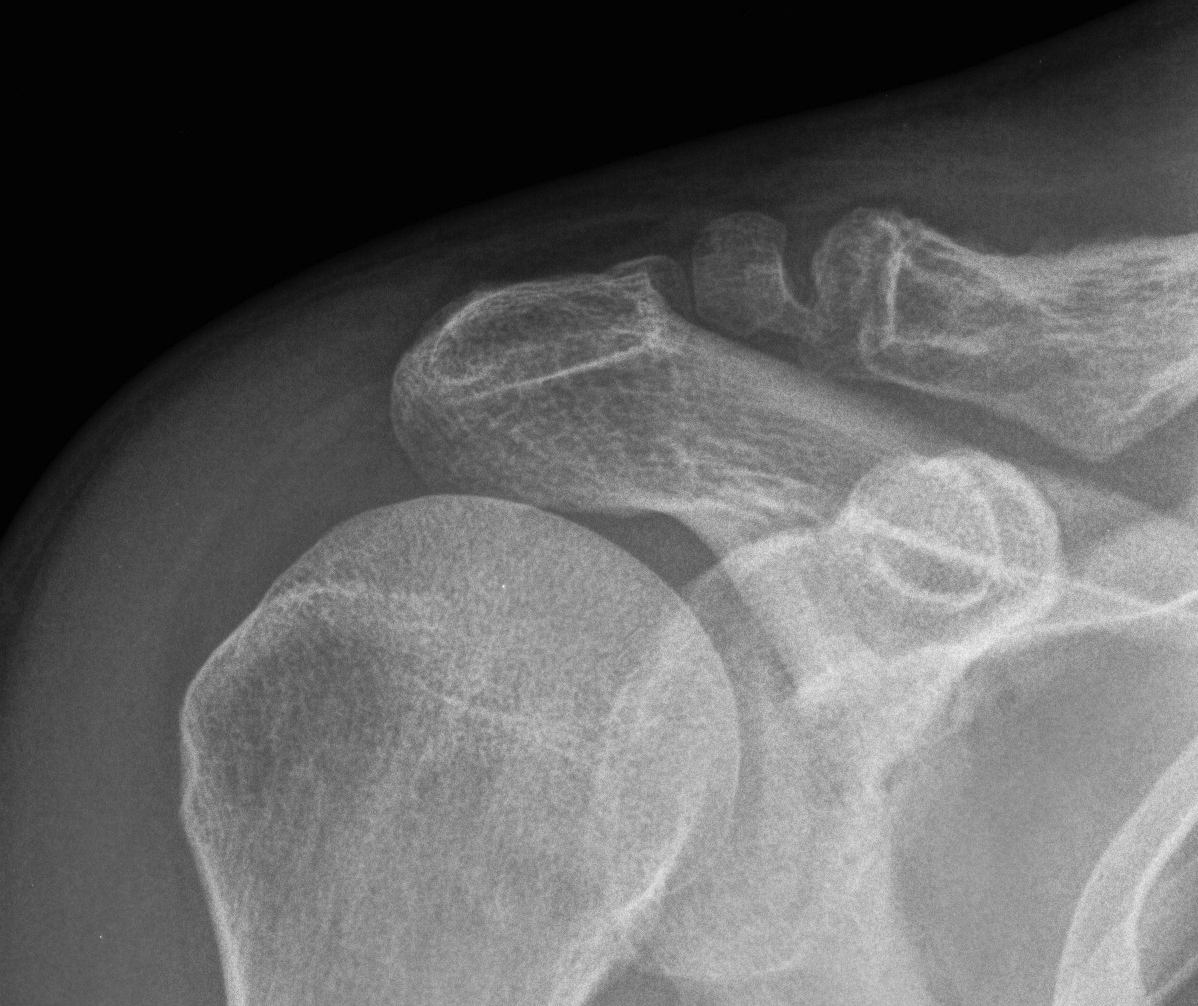

Nonunion

Robinson and Cairns JBJS Am 2004

- cohort of 100 displaced Type II fractures treated nonoperatively

- 11 had symptomatic nonunion

- 21 had asymptomatic nonunion

- reasonable outcome scores with nonunion

- recommended non operative treatment in middle aged / elderly